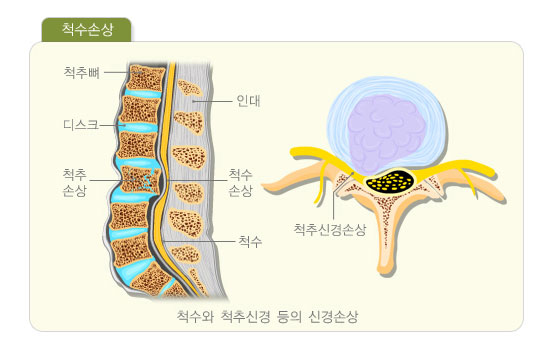

교통사고, 낙상, 산업재해사고 등의 심한 외상에 의해 목,허리의

척추뼈에 골절과 심한 인대(연부조직)손상이 동반되는 경우를 말합니다. 흔히 발생되는 부위는

목(경추부), 등,허리(흉요추부)이며 골다공증성 골절에 비해 비교적 젊은 나이에서 발생됩니다.

그러므로 손상이 심한 경우가 많으며 신경마비 등이 동반되는 심한 형태의 골절도 발생됩니다.